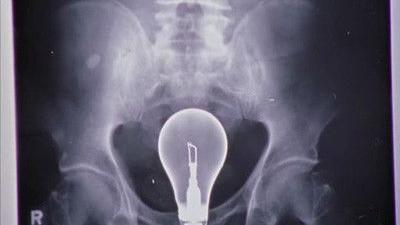

Molly travaille sur la résolution des conflits en milieu hospitalier et choisit le docteur Cox comme sujet d'étude. Pourvue de bonnes intentions, elle tente de réconcilier JD et Elliot, en compétition pour décrocher le poste de Chef des internes. Pendant ce temps, Cox, JD et le concierge essaient de résoudre le mystère de l'hôpital : comment extraire une ampoule du ventre d'un patient sans la briser ?